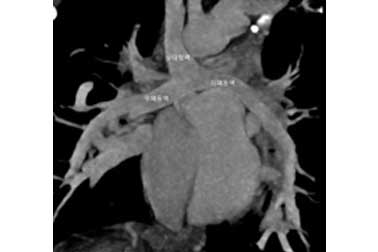

(2) 상대정맥-폐동맥 단락술 후의 CT 소견

상대정맥-폐동맥 단락술 후의 CT 소견